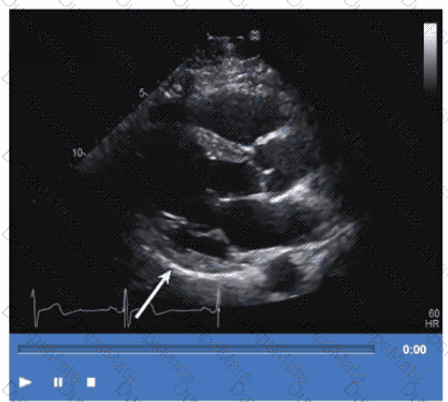

Questions 30

Which adjustment should be made to optimize this video?

AE-Adult-Echocardiography Question 30

Options:

A.

Increase compression

B.

Decrease overall gain

C.

Increase time gain compensation in the near field

D.

Decrease time gain compensation in the far field